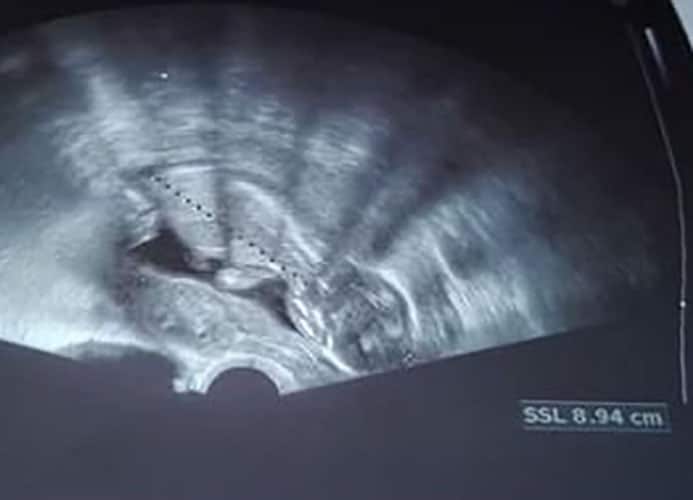

Ultraschallbilder aus dem 2. Trimester (13. bis 28. SSW)

Im 2. Trimester bekommt man oft die schönsten "Ganz-Körper" Ultraschallbilder. Das Baby ist nun so groß, dass man alles gut erkennen kann und noch nicht zu groß, so dass es noch ganz auf das Bild passt. In dieser Zeit lässt sich meist das Geschlecht bestimmen, wobei manche Babys es einfach nicht preis geben wollen und sich immer so drehen, dass man nichts erkennen kann.